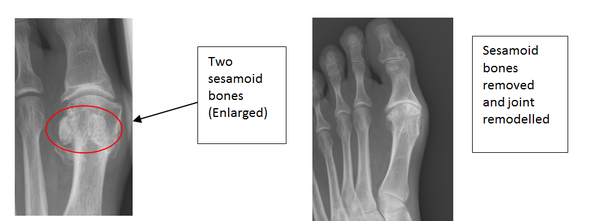

Sesamoidectomy

There are two small bones under the ball of the big toe called sesamoids. Removing these bones can help increase the range of movement and reduce the pain experienced by freeing up the joint. At the same time the bony prominences around the joint are removed. This procedure aims to reduce pain and maintain movement. It is unlikely to resolve the joint pain completely.